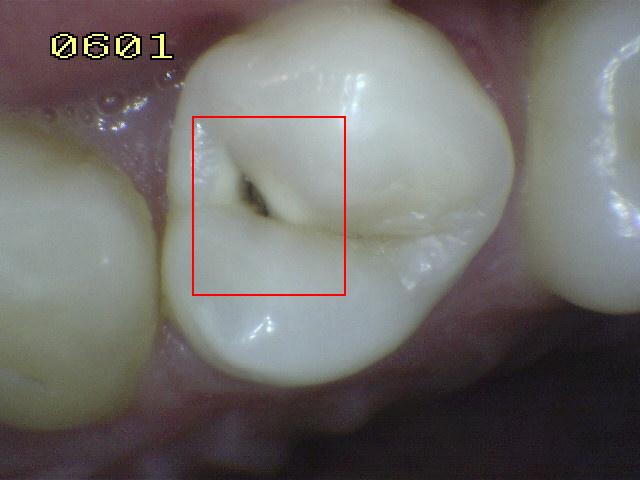

Código 3:

Ruptura localizada del esmalte debido a caries sin dentina visible

- El diente visto en estado

húmedo pueden tener una clara opacidad de caries (lesión de

mancha blanca)

y / o decoloración marrón de caries que es más ancha que la

fisura natural y la fosa, que no es consistente con la

apariencia clínica de esmalte sano. Una vez seco, se

observa una pérdida de estructura dental cariada en la

entrada, o dentro de la fosa o fisura . Esto se ve

visualmente como evidencia de desmineralización en la

entrada o dentro de la fisura o fosa, y aunque la fosa o

fisura puede aparecer sustancialmente más ancha que lo

natural, la dentina no es visible en las paredes o la base

de la cavidad ó discontinuidad .

-

En caso de duda, o

para confirmar la evaluación visual, la sonda de la OMS /

IPC / PSR puede ser

utilizada con cuidado a través de la superficie del diente,

para confirmar la presencia de una cavidad ( < 0,5mm.de

profundidad) al parecer limitada al esmalte . La

identificación de la cavidad se consigue deslizando el

extremo de la bola a lo largo de la fosa o fisura

sospechosa.